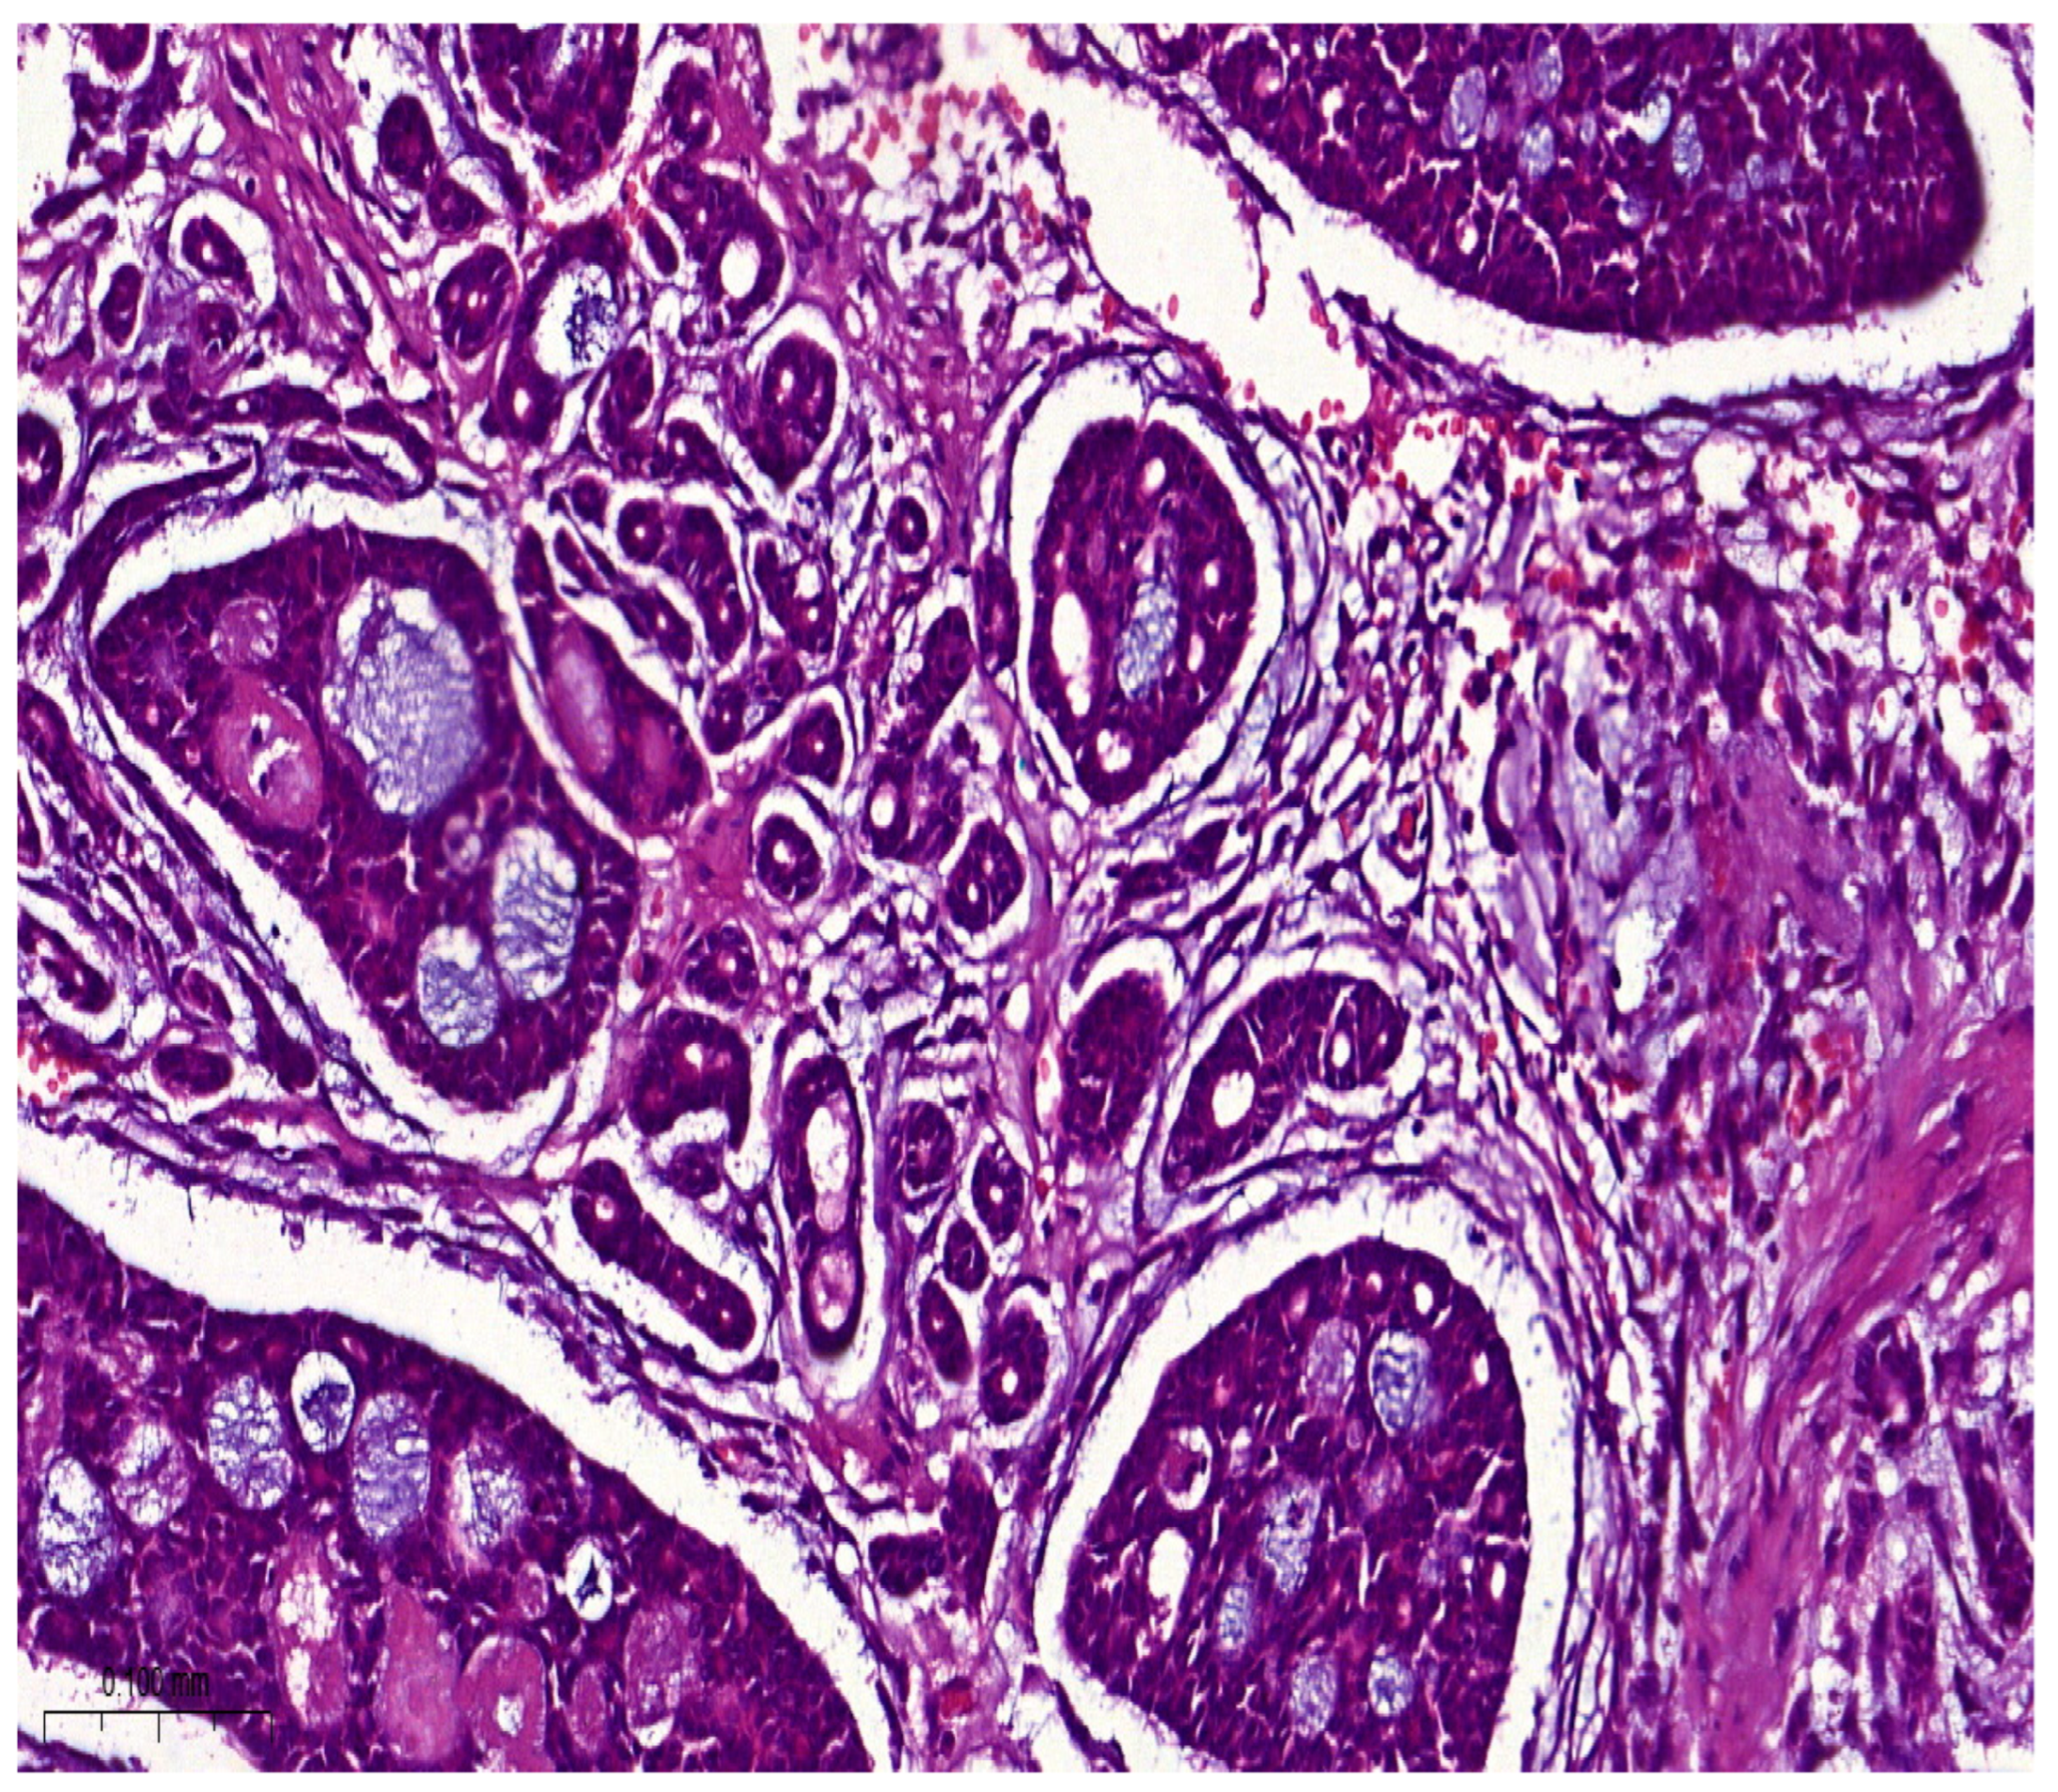

Histologically, salivary nonsolid AdCCs showed biphasic cell populations arranged in alternate cribriform and tubular architectures (Figure 1). The cribriform pattern demonstrated nests of neoplastic cells with hyperchromatic, angulated nuclei arranged in microcystic and macrocystic spaces. These pseudocystic cavities were occasionally filled with hyaline or basophilic mucoid material. The histologic features in the major salivary glands did not differ much from those in the minor salivary glands. However, solid nests of AdCC favored submucosal infiltration in the minor salivary glands (Figure 2, Case #15). Sinonasal AdCC revealed nests of cribriform and solid areas, while extensive hyalinization was recapitulating a jigsaw puzzle-like pattern (Figure 3). The cells of sinonasal AdCC were sometimes basaloid, with dark, hyperchromatic nuclei. The cells were typically arranged in a palisading pattern around the cystic spaces. A few salivary AdCCs revealed basaloid cells arranged in solid growth patterns that were insufficient for diagnosis as high-grade AdCCs. Mammary SB-AdCC revealed areas of cribriform, a solid growth pattern (>90%), and a basaloid appearance, with myxoid or hyalinized stroma. Ductules were present within the tumor islands. Small cysts and pseudoglandular structures were occasionally seen (Figure 4). This variant is characterized by the presence of small, basal-like cells with scant cytoplasm. The basaloid variant was associated with a higher risk of metastasis and a poorer prognosis. All neoplastic cells were positive for IHC SOX10, CK7, CD117, p63, and KI67. The clinical and molecular findings are shown in Table 1. There, all of the AdCC cases had MYB rearrangements detected by fluorescence in situ hybridization (FISH), which is a common genetic alteration observed in AdCC. Specifically, MYB was found to be fused with NFIB and/or KMT2C/KMT2D in AdCC cases from sinonasal and minor SG sites. MYB::NFIB fusion is a well-known molecular alteration that occurs in approximately 30–70% of AdCC cases and has been associated with better prognosis compared to cases without this fusion. On the other hand, MYB::KMT2C/D fusions were less common but have also been reported in cases from salivary and sinonasal AdCCs. Although this is the first study to report this finding, its clinical significance is yet to be fully elucidated. In addition to FISH, some AdCC cases were also analyzed using next-generation sequencing. In Table 1, NGS was performed in several AdCC cases from sinonasal, minor SG, and parotid gland sites. MYB::NFIB and MYB::KMT2D fusions were detected in these cases, which is consistent with the FISH results. Notably, some cases were not analyzable by NGS, which may be due to various reasons such as low DNA quality or quantity. The median score for Group 1 was 70 (IQR: 60–80), the median score for Group 2 was 85 (IQR: 75–90), and the median score for Group 3 was 60 (IQR: 55–70). The results indicate that there was a significant difference between Group 1 and Group 3 (p < 0.05) and between Group 2 and Group 3 (p < 0.05) but not between Group 1 and Group 2 (p > 0.05). This suggests that the solid mammary AdCCs with basaloid features (Group 3) have different characteristics compared to the other two groups.

Figure 1.

Salivary AdCC showed biphasic cell populations arranged in alternate cribriform and tubular architectures. Pseudocystic cavities were occasionally filled with hyaline or basophilic mucoid material (H&E stain; magnification ×5).